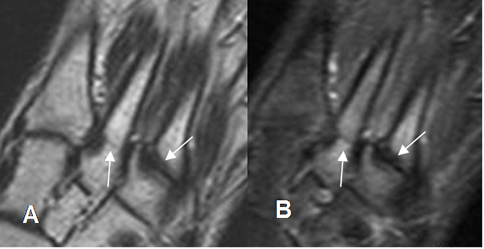

Fig 36 A. Fractura de stress.

A: RM coronal en T1 y B: RM coronal en STIR. Fracturas no desplazadas y de evolución aguda, en las bases del 2º y 3º metatarsianos.